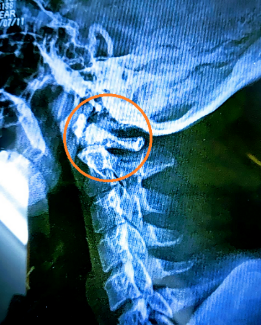

めまいの原因は「頚椎」にある可能性があります

そのような場合、当院では 頚椎(首の骨)の歪みや機能低下 に着目します。

なぜ頚椎がめまいを引き起こすのか

頚椎は、

・脳へ向かう血流の通り道 ・自律神経が集中している部位 ・平衡感覚に関わる神経経路

が集まる非常に重要な場所です。

スマートフォンやパソコン作業、猫背姿勢、ストレスなどにより頚椎のバランスが崩れると、

✔ 神経伝達の乱れ ✔ 脳への血流低下 ✔ 自律神経の不安定

が起こり、めまいとして現れることがあります。

これを「頚性めまい」と呼ぶこともあります。